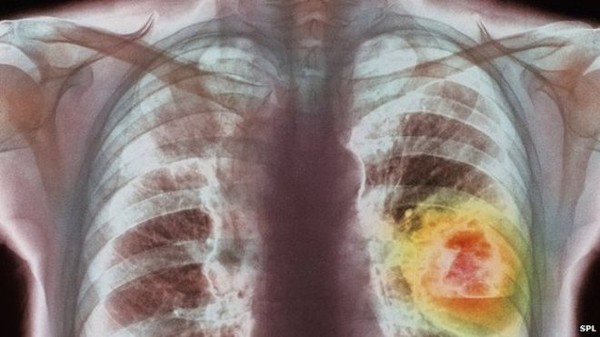

Ung thư phổi xâm nhập, tàn phá cơ thể như thế nào?

Tỷ lệ người bị ung thư phổi ngày càng gia tăng, trong đó, hút thuốc lá hoặc tiếp xúc với khói thuốc trong thời gian dài được coi là tác nhân chính.